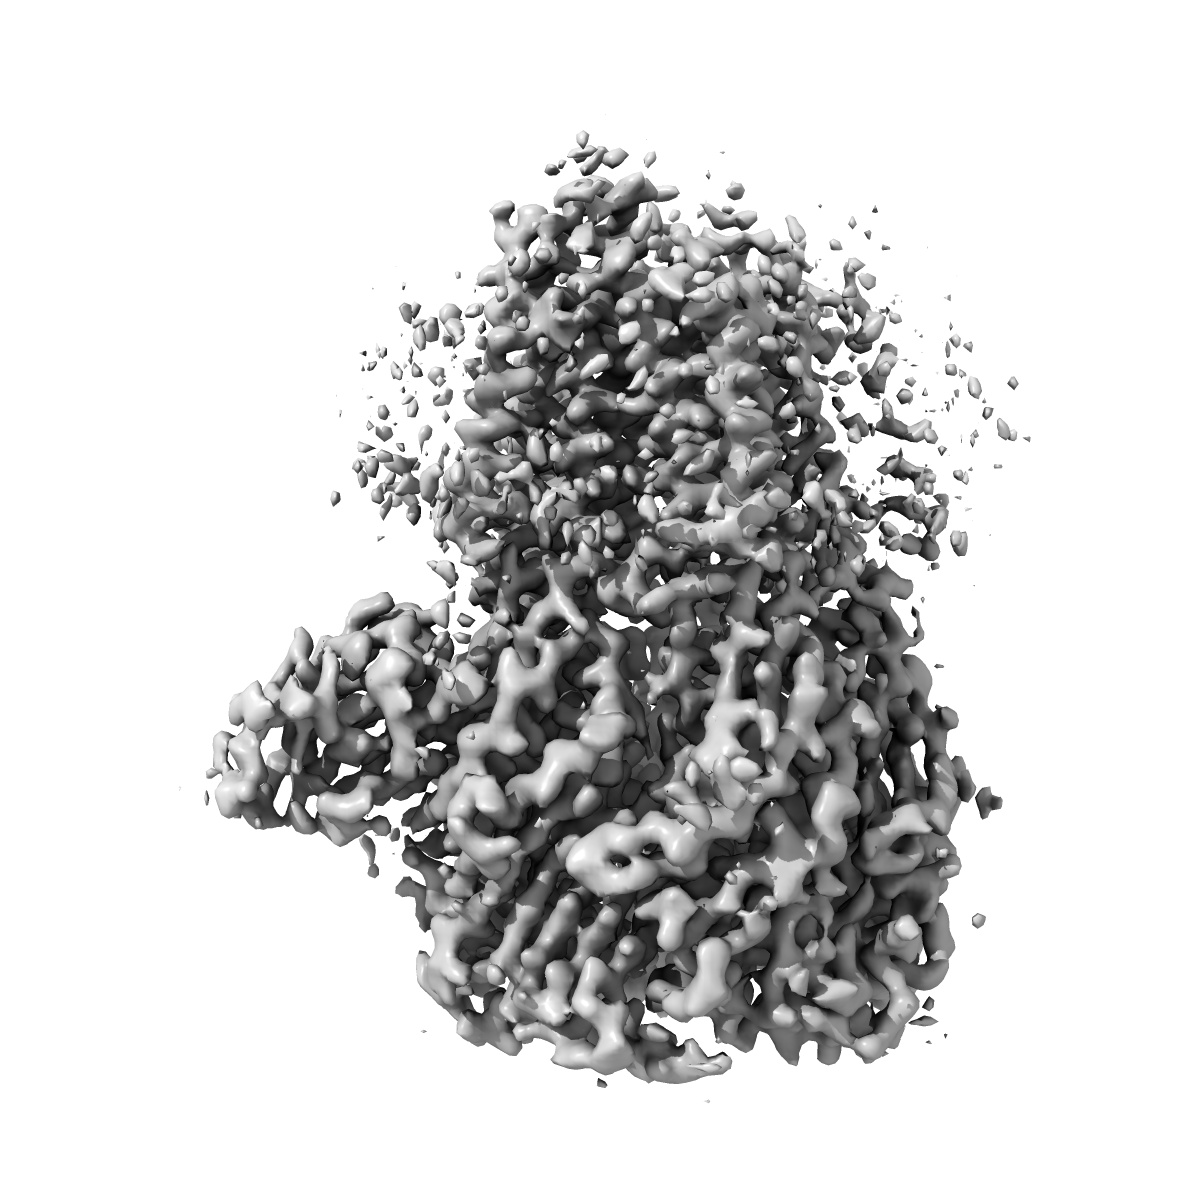

CryoEM structure of human full-length alpha1beta3gamma2L GABA(A)R in complex with diazepam (Valium), GABA and megabody Mb38.

Single-particle3.58 Å

Sample: Human full-length heteromeric alpha1beta3gamma2L GABA(A)R in complex with diazepam (Valium), GABA and megabody Mb38.

Fitted models: 6hup